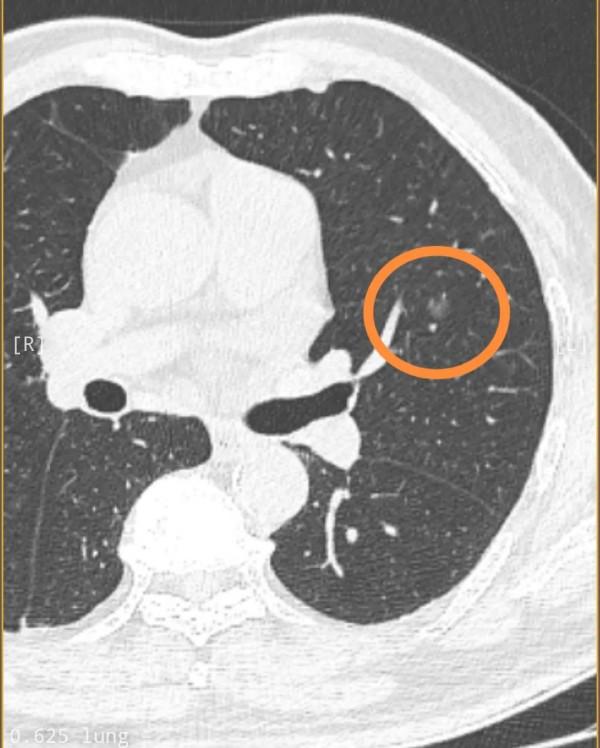

患者,男性,分別於今年2021年9月份和2021年12月份做的CT,且CT結果顯示相關肺結節大小沒有發生顯著變化。9月份醫生診斷意見吃消炎藥,三個月後複診。12月在同一家醫院同一醫生診斷為肺癌。煩請大夫說說您的意見,如有手術必要,最好採取哪種方式,楔形還是其他方式,謝謝。

閱片見兩肺多發磨玻璃結節病灶,其中右下葉2處紅色圈起來的都考慮是浸潤性腺癌,不能再觀察隨訪了,得儘早手術,建議右下葉切除;中葉綠色圈起來的是良性的可能性大,可隨訪,但若反正右側手術了,順便定位後區域性切掉也可考慮;左上葉桔色圈起來的考慮原位癌或不典型增生可能性大,目前風險不高,位置也不好,若隨訪有進展再來考慮怎麼處理它。以上意見供參考!